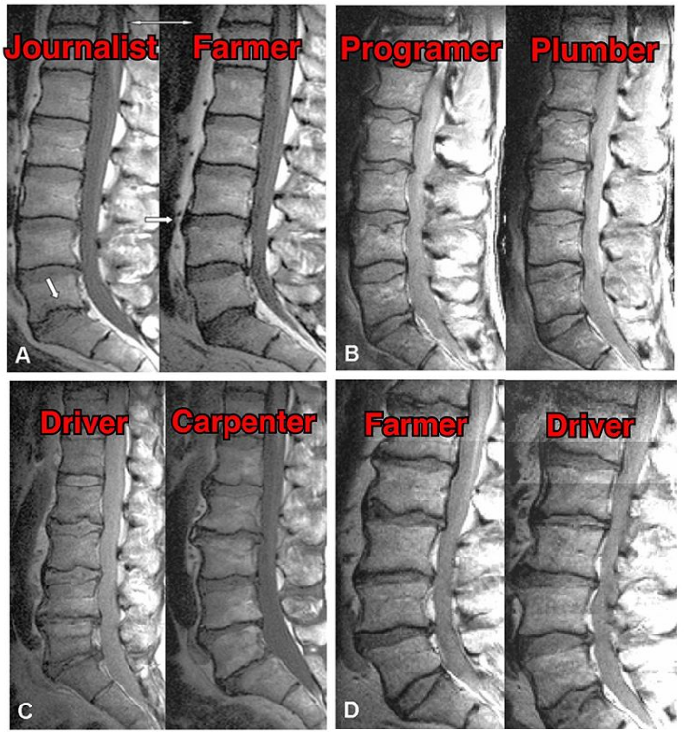

И ведь действительно, одни «спинальники» обвиняют в своих проблемах сидячую работу, из-за которой «протрузии вылазят», а другие наоборот говорят, что в грыжах и протрузиях виновата тяжёлая нагрузка. В данном же обзоре были изучены позвоночники близнецов, ведущих разный образ жизни. На рисунке ниже можно посмотреть МРТ снимки генетически идентичных близнецов:

а) журналист и фермер;

в) программист и сантехник;

с) водитель и плотник;

d) фермер и водитель.

Условно говоря, один позвоночник целый день сидит, а второй целый день навоз таскает, и оба выглядят одинаково. Потому что генетика решает многое! А боли в спине от сидячей работы, либо чрезмерной физической нагрузки - это уже совсем другая история, и может быть никак не связана непосредственно с «грыжами».